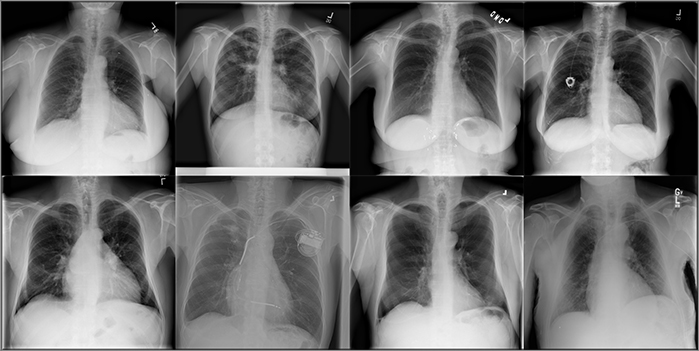

En el nuevo estudio, publicado en Proceedings of the National Academy of Sciences (PNAS), los científicos santafesinos utilizaron bases de datos públicas: una curada por investigadores de la Universidad de Stanford, con 65.240 pacientes con un total de 224.316 imágenes, y otra publicada por el National Institutes of Health de Estados Unidos (NIH) que incluye 30.805 pacientes y un total de 112.120 imágenes.

Estas bases de datos están compuestas por radiografías de tórax de todos los pacientes, acompañadas por el correspondiente diagnóstico médico que indica si poseen o no distintas patologías comunes del tórax que pueden afectar tanto a hombres como mujeres, por ejemplo hernias, neumonía, fibrosis, enfisema, edema, engrosamiento pleural y neumotórax.

Los modelos utilizados están basados en redes “neuronales” convolucionales profundas y son entrenados para predecir si esas patologías del tórax están presentes o no en la imagen. En sus experimentos, los científicos del CONICET y de la UNL generaron conjuntos de datos considerando distintos porcentajes de hombres y mujeres, y luego evaluaron el rendimiento de cada modelo a la hora de predecir el diagnóstico en nuevas imágenes de hombres y mujeres por separado, cuantificando el rendimiento en ambos grupos.